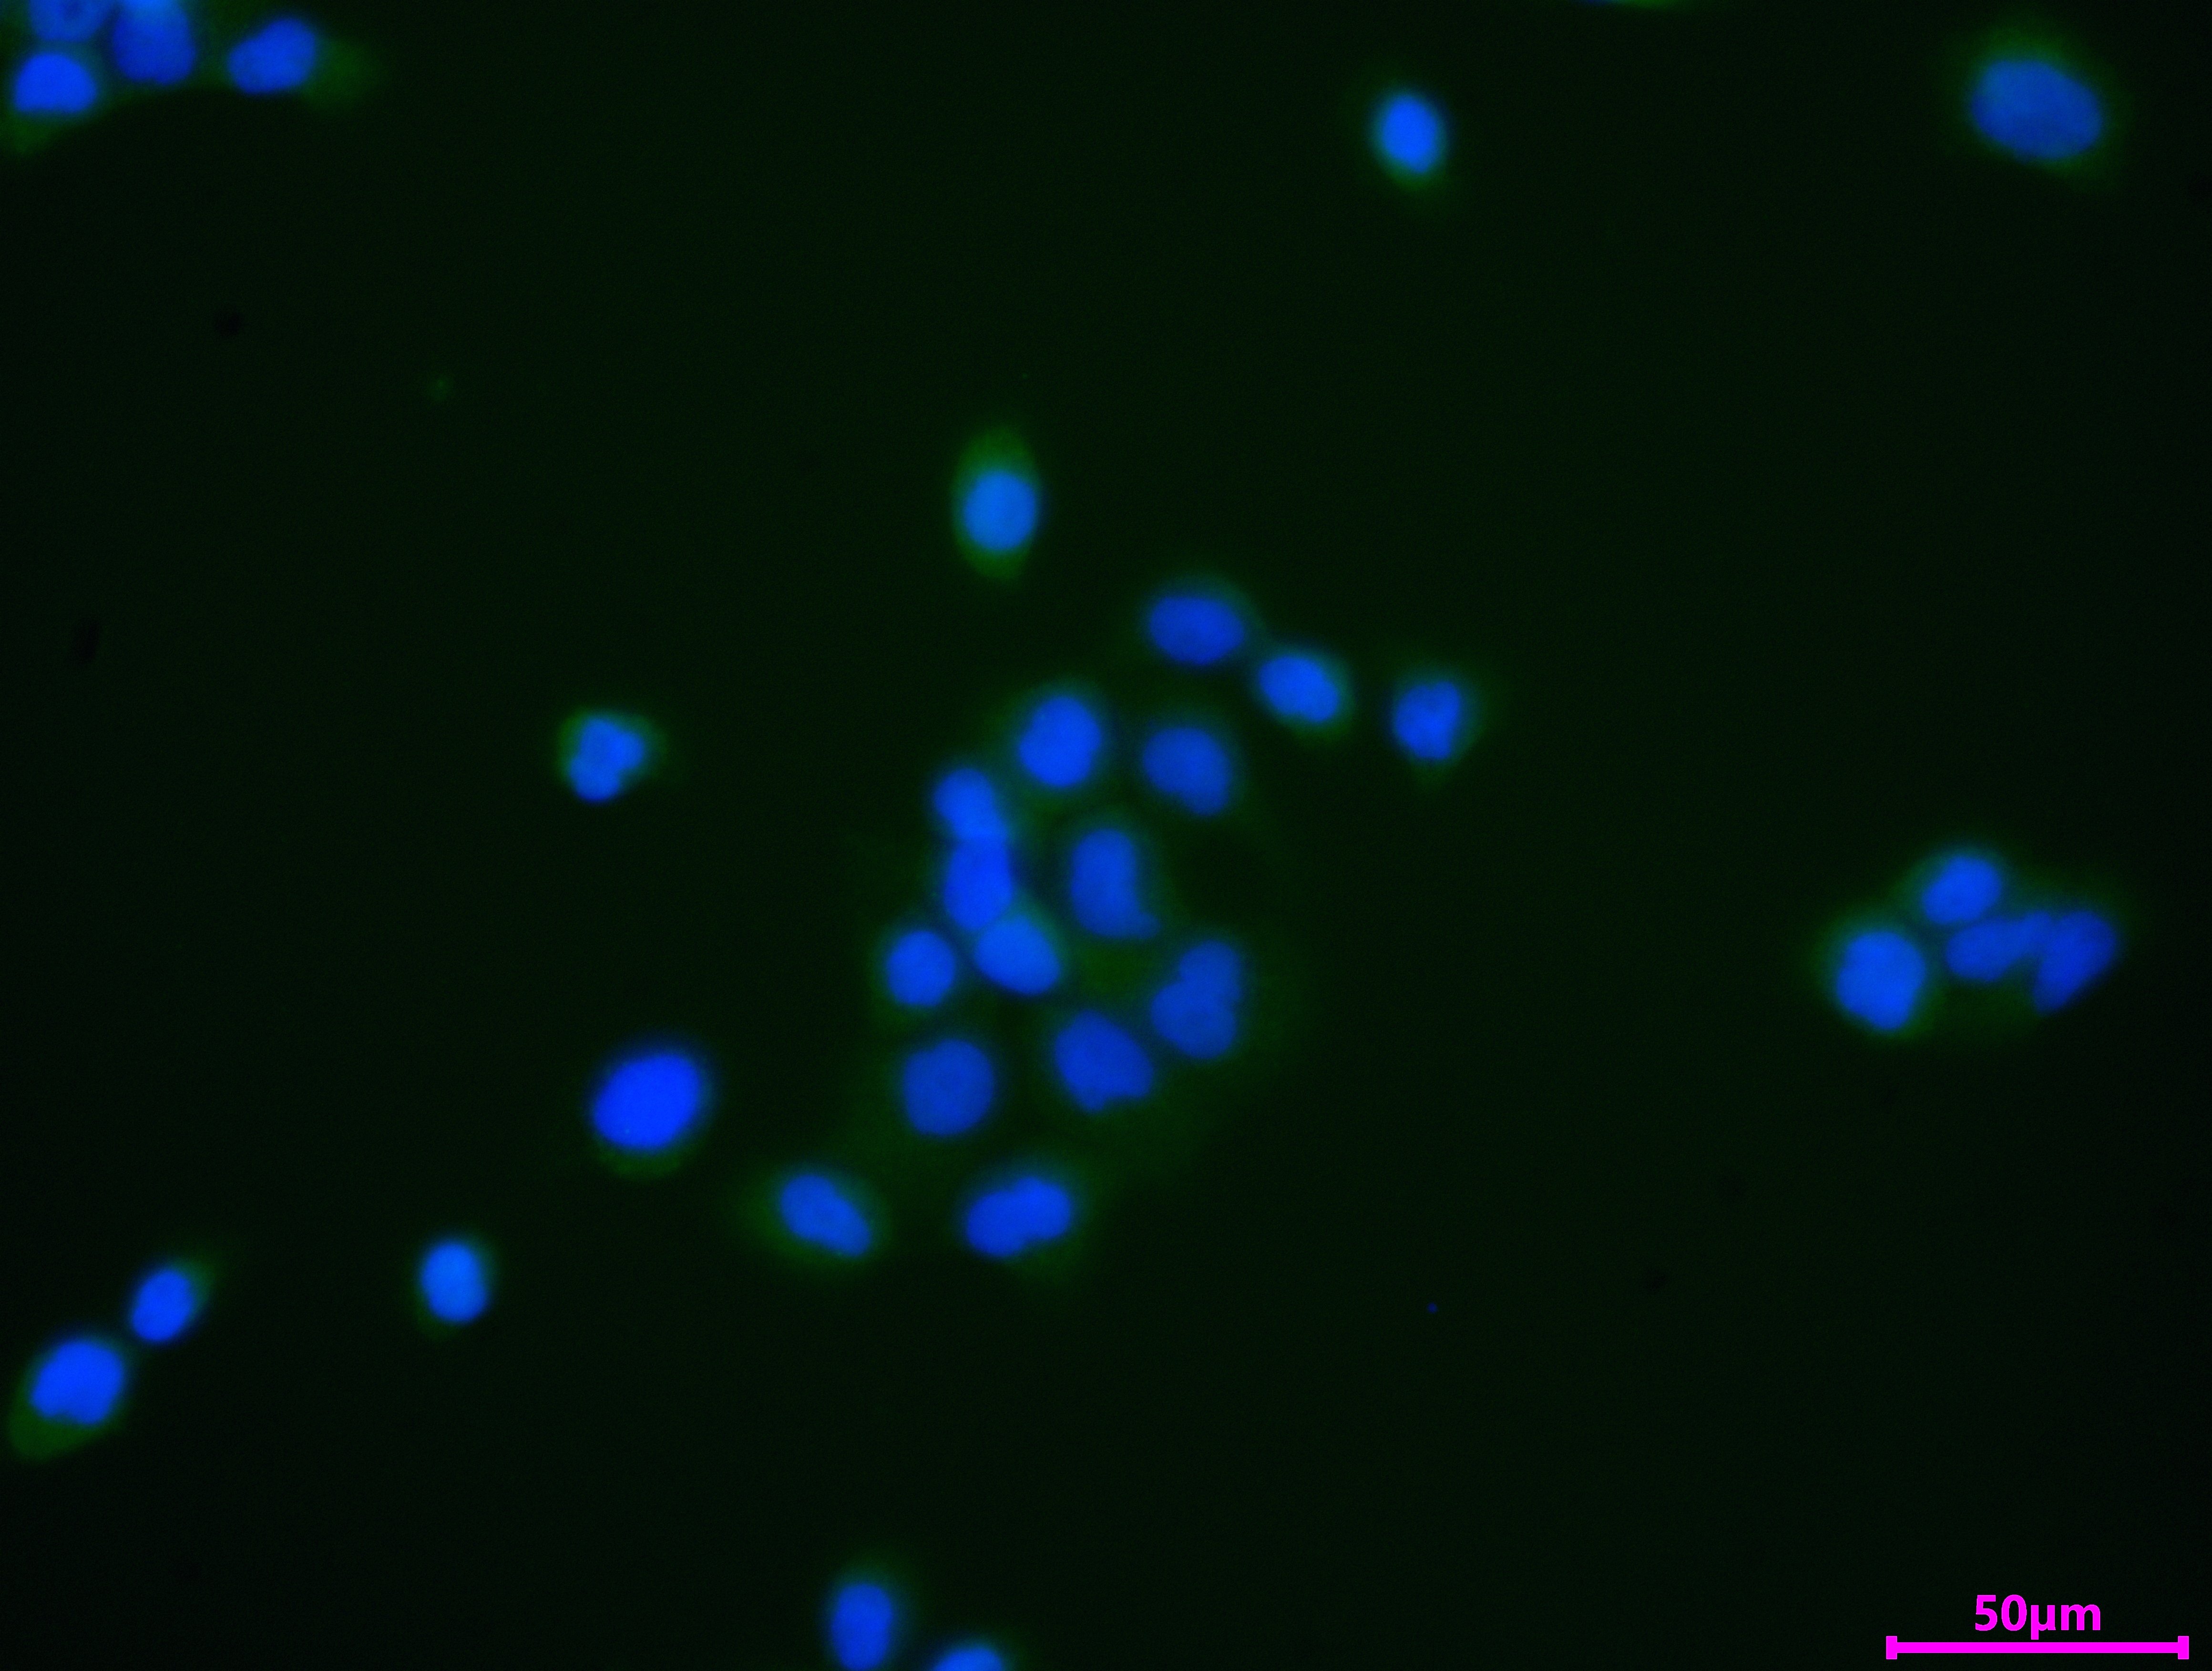

Immunofluorescent analysis of Hela cells using CSB-PA015249LA01HU at dilution of 1:100 and Alexa Fluor 488-congugated AffiniPure Goat Anti-Rabbit IgG(H+L)